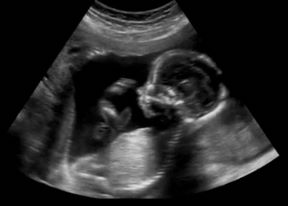

PRVI BEBIN UDAH: U maternici vježba disanje, a prvi plač je premijera